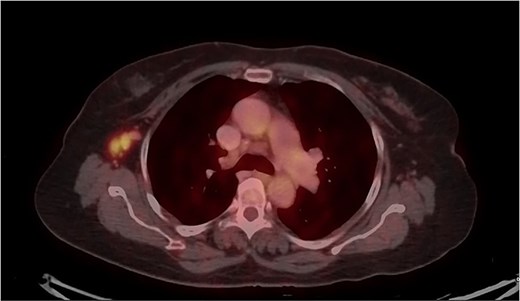

Mammography revealed an asymmetrical density in the upper outer quadrant of the right breast with BIRADS V classification. Ultrasonography identified an irregular hypoechoic lesion measuring 3.8 × 2.5 cm in the right breast. Additionally, multiple enlarged axillary lymph nodes with cortical thickening were seen, the largest measuring 1.02 cm in diameter. A core needle biopsy of the breast lesion demonstrated features of invasive carcinoma, not otherwise specified (NOS), Grade II based on the Nottingham grading system. Immunohistochemistry revealed the tumor to be ER-positive (78%), PR-negative, Her2Neu-negative, and Ki67–21%, confirming it as Luminal A subtype. The excised axillary lymph nodes exhibited caseating granulomatous inflammation, consistent with tuberculosis (Fig. 1). Acid-fast bacilli (AFB) testing further confirmed the diagnosis of TB. Pre-surgical imaging revealed metabolically active areas in the breast lesion and axillary lymph nodes with no evidence of systemic metastases (Figs 2 and 3).

PET-CT axial view of the thorax, indicating a metabolically active lesion in the right axillary region, involving the right axillary lymph nodes.